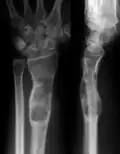

-

X-ray showing calcified enchondromas localized in finger a 37-year-old patient affected with Ollier disease -

X-ray showing enchondromas localized in the humerus of a 37-year-old patient affected with Ollier disease -

X-ray showing enchondromas localized in the lower part of the radius of a 37-year-old patient affected with Ollier disease -